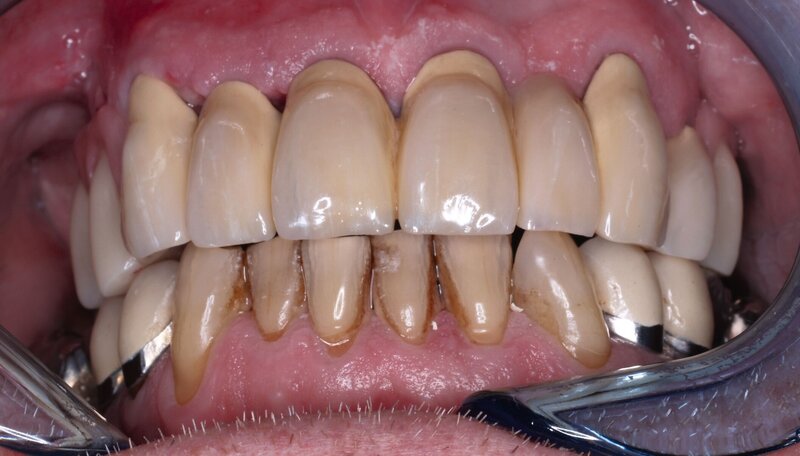

Der Patient stand unter der Dauermedikation von Metformin 500 mg, Ramipril 5 mg, Torasemid 10 mg, Metohexal 47,5 mg, Simvastatin 20 mg, Tamsulosin 0,4 mg und 3 mg Marcumar (INR 2,5–2,8) bei Zustand nach einer Bypass-Operation im Jahr 2019. Klinisch zeigten sich im Oberkiefer insuffiziente, verblockte und verblendete NEM-Kronen mit beidseitigen Gold-Extensionen distal, die über Geschiebe mit dem anterioren Anteil verschraubt waren (Abbildungen 1 und 2). Der Patient berichtete, dass die vorhandenen Kronen und Brücken 1984 eingesetzt worden seien.

Besonders auffällig war eine Dezementierung, die klinisch durch rechtsseitigen Druck und Zug mit einer Pinzette und daraufhin austretende Sulkusflüssigkeit in Regio 14 detektiert wurde. Da entsprechend des synoptischen Behandlungskonzepts [Naumann et al., 2010] bei prothetischer Neuversorgung eine gesamte Evaluation der Restpfeiler erfolgen muss, wurden zunächst die Kronen im Oberkiefer durch Schlitzen und Aufbiegen entfernt. Erst danach ließ sich deren Erhaltungswürdigkeit abschließend beurteilen.

So war der Zahn 14 tief kariös zerstört und nicht-erhaltungswürdig, was mit dem Bild der wahrscheinlich seit Längerem bestehenden Dezementierung korrelierte (Abbildung 3). Die Brücken im Unterkiefer wurden als suffizient befundet. Die Ruheschwebelage wurde mithilfe des Zielinsky-Zirkels auf 2 mm bestimmt. Parodontologisch zeigten sich stabile Verhältnisse. Ein Parodontaler Screening-Index (PSI) wurde erhoben (3-1-1-1-2-2). Der hier auffällige Zahn 14 wurde bereits zuvor beim klinischen Befund als nicht-erhaltungswürdig eingestuft und im Verlauf extrahiert.